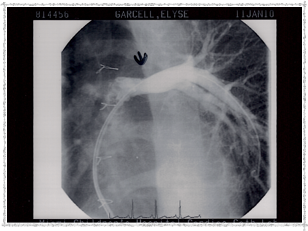

Second Catheterization — Dr. Danyal Khan

In 2010, Elyse underwent her second catheterization procedure, overseen by Dr. Danyal Khan at Miami Children's Hospital. The procedure focused on her pulmonary arteries, and these images show the before and after.

2010 - Left Pulmonary Artery Before

Left Pulmonary Artery — Before

2010 - Before Procedure

Before the procedure